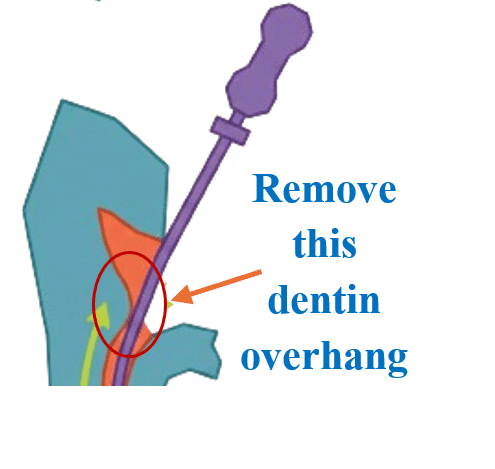

Step 2 — Create space coronally

Use ultrasonic tips to create a 0.5–1 mm cuff around fragment.

Step 1 — Improve access

Create straight-line access